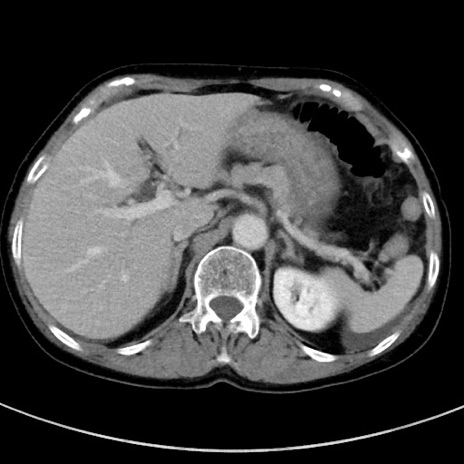

症例23(横断像)

【症例】70歳代女性

【主訴】下腹部痛・嘔吐

【現病歴】2日前より腹痛あり。昨日嘔吐あり。症状改善しないため来院。

【既往歴】胃GISTに対して胃部分切除後。

【身体所見】BT 37.1℃、BP 128/77mmHg、腹部:平坦・軟、下腹部に圧痛あり。

【データ】WBC 10200、CRP 0.31